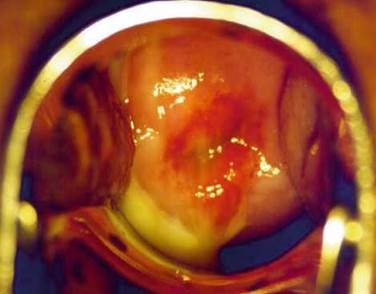

This is an uncommon cause of discharge of unknown aetiology. The appearance is that of trichomoniasis, there being a marked vaginitis and profuse yellow discharge (Figure 6.2). Colposcopic examination of the vagina and cervix may show a macular pattern (as is often seen in trichomoniasis- so-called "strawberry cervix"). Gram stain and microscopy of the discharge shows an absence of lactobacilli with cocci-form bacteria and vaginal basal epithelial cells present (as seen in a post menopausal woman with an atrophic vaginitis). There is often a good response to intravaginal Clindamycin cream.

Figure 6.2. Macular vaginitis - seen in some cases of Trichomoniasis and desquamative vaginitis